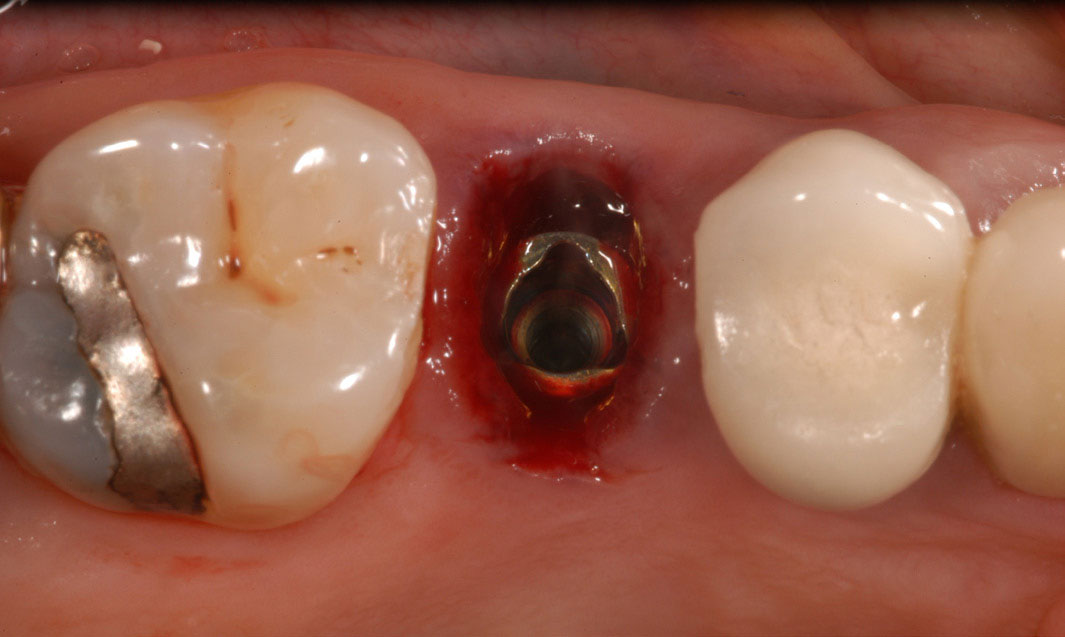

Figure 17– A zircon (white) abutment was attached immediately after extraction and implant placement.

Figure 17

Figure 18 – Immediate placement of temporary crown over the abutment; laser crown lengthening was performed on the adjacent teeth to improve gingival symmetry

Figure 18

A dental implant most closely replicates natural tooth structure. Once it is osseointegrated, many patients cannot differentiate an implant from a natural tooth. Furthermore, dental implants do not decay or need root canal therapy. Even though the cost is slightly more than a bridge, it is an investment for the future, as implants usually last longer than a bridge. A 10-year report on posterior single implants shows a success rate of 97%.33 Once an implant is placed, the osseointegration and tissue healing time of approximately 4 months is necessary before a final crown is placed. A temporary crown can be placed the same day the implant is placed, but this is only for esthetics, not for function (Figure 15 through Figure 19).